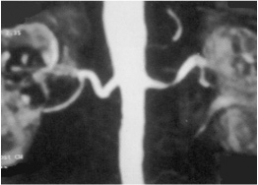

Η αξονική και η μαγνητική αγγειογραφία οι οποίες είναι πολύ αποτελεσματικές μέθοδοι αγγειακής απεικόνισης. Δίνουν πληροφορίες για την ύπαρξη αρτηριακών αποφρακτικών βλαβών σε όλο το αρτηριακό δέντρο.

Η αρτηριογραφία η οποία είναι επεμβατική μέθοδος και για τον λόγο αυτό πραγματοποιείται συνήθως προεγχειρητικά ή στην περίπτωση ενδαγγειακής θεραπείας.